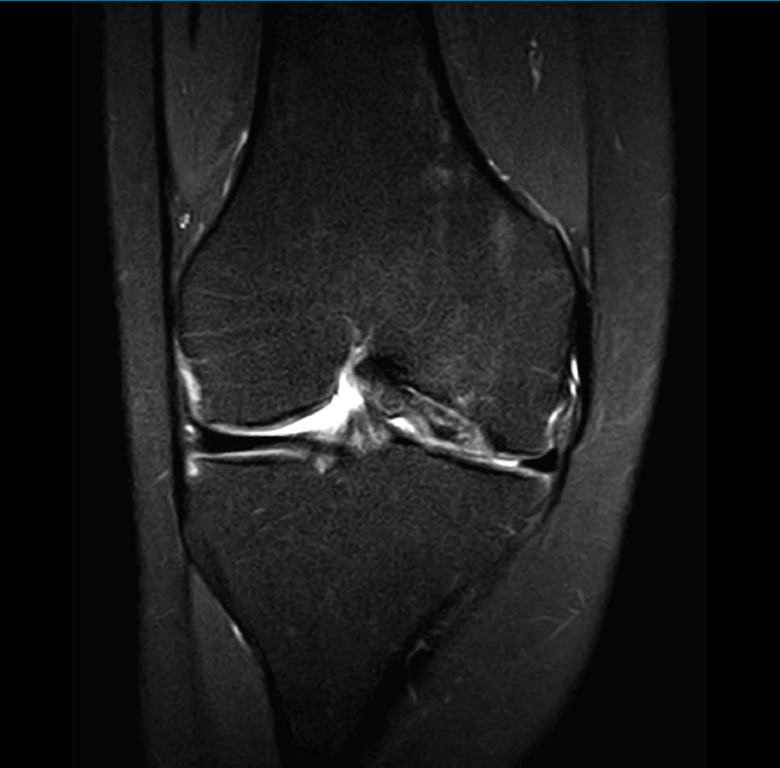

En la osteocondritis se aprecia una lesión subcondral caracterizada por resorción ósea, colapso y la formación de un secuestro.

El estudio por RM es una herramienta valiosa para diagnosticar e identificar las lesiones del cartílago. Conocer el aspecto del cartílago y saber cuánto y cuándo se lesiona, basándose en las clasificaciones actuales, permiten al radiólogo proporcionar la máxima información al clínico(20).

Figura 53. Corte de secuencia sagital (A) y axial (B) T2 Fat-Sat de RM de rodilla: lesiones osteocondrales en el fémur y la rótula.

Numerosos estudios demuestran la utilidad de la RM para definir la estabilidad o inestabilidad de la lesión en la osteocondritis, destacando su carácter no invasivo y la capacidad de valorar la progresión y la respuesta al tratamiento(21)(Figuras 53 y 54).

Figura 54. Corte de secuencia T1 y T2 Fat-Sat coronal de resonancia magnética: gran osteocondritis en el cóndilo femoral interno con edema en la medular adyacente.